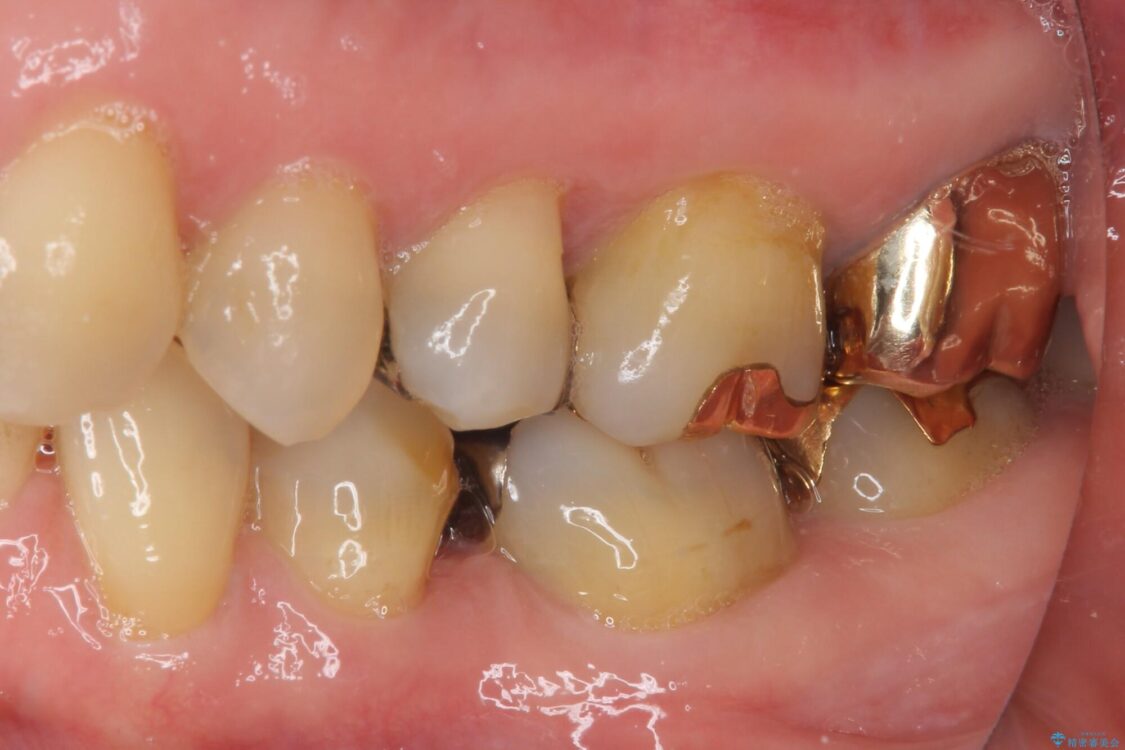

奥歯の銀歯が外れてしまったため、セラミック治療を希望された患者様です。

セラミックインレーによる修復治療を実施しました。

正面から見える場所であったため、セラミックインレーで自然な口元にすることができました。

治療途中

• 外れてしまった銀歯 セラミックインレーで自然な仕上がりに 治療途中画像